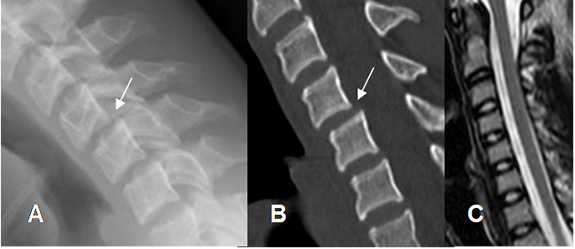

La TAC es la modalidad de elección en la valoración inicial, de la columna cervical en pacientes politraumatizados y ha demostrado ser costo-efectiva. (38, 41, 42). Es mas sensible que la Rx simple para detectar fracturas y permite realizar reconstrucciones 3D y caracterizar las lesiones. (40, 41). (Fig 173 y 174).

Fig 173. Fractura no vista en Rx.

A: Rx lateral. Rectificación cervical, sin desalineación, ni fracturas. Calcificación en la parte anterior del disco C5-C6.

B: TAC axial. Fractura oblicua y no desplazada en la lámina izquierda de C5, no sospechada con la Rx.

Fig

174. Fractura con TAC.

A: Rx lateral. Aumento del espacio pre-vertebral, no encontrando fracturas, ni desalineación.

B: TAC reconstrucción sagital y C: TAC reconstrucción en 3D. Fractura en la base de la odontoides.